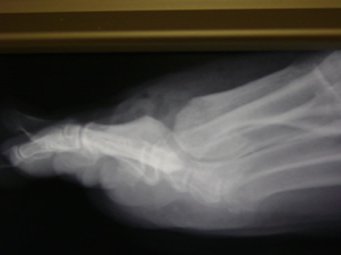

How do we diagnose arthritis in the big toe joint?

This is done with a simple X-ray. The X-ray will be assessed, and the spurring, loss of joint space and various other signs are apparent to see. During a consultation, the joint will be evaluated for range of motion, and the presence of spurring will be checked. The joint will often creak or grind as it is moved.